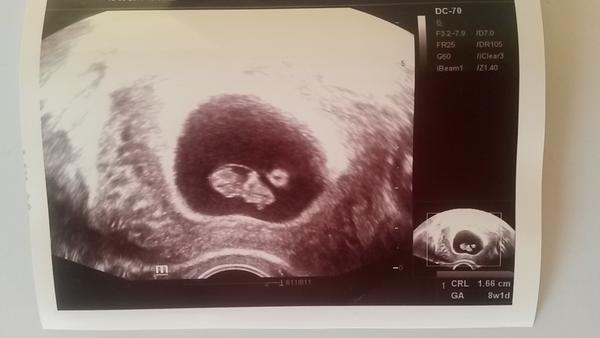

Ahoj holky, včerejší kontrola dopadla dobře 😀 Podle MS jsem 9+1, podle utz je o týden míň. Vše vypadá v pořádku, srdíčko bilo 😍 Mám radost, i když strach je tam pořád, ale to je asi normální. Včera měl přítel svátek, tak to byl pěkný dárek 🙂 A taky to shodou okolností včera bylo přesně 5 měsíců od revize. Věřím, že tentokrát už to vyjde 👶